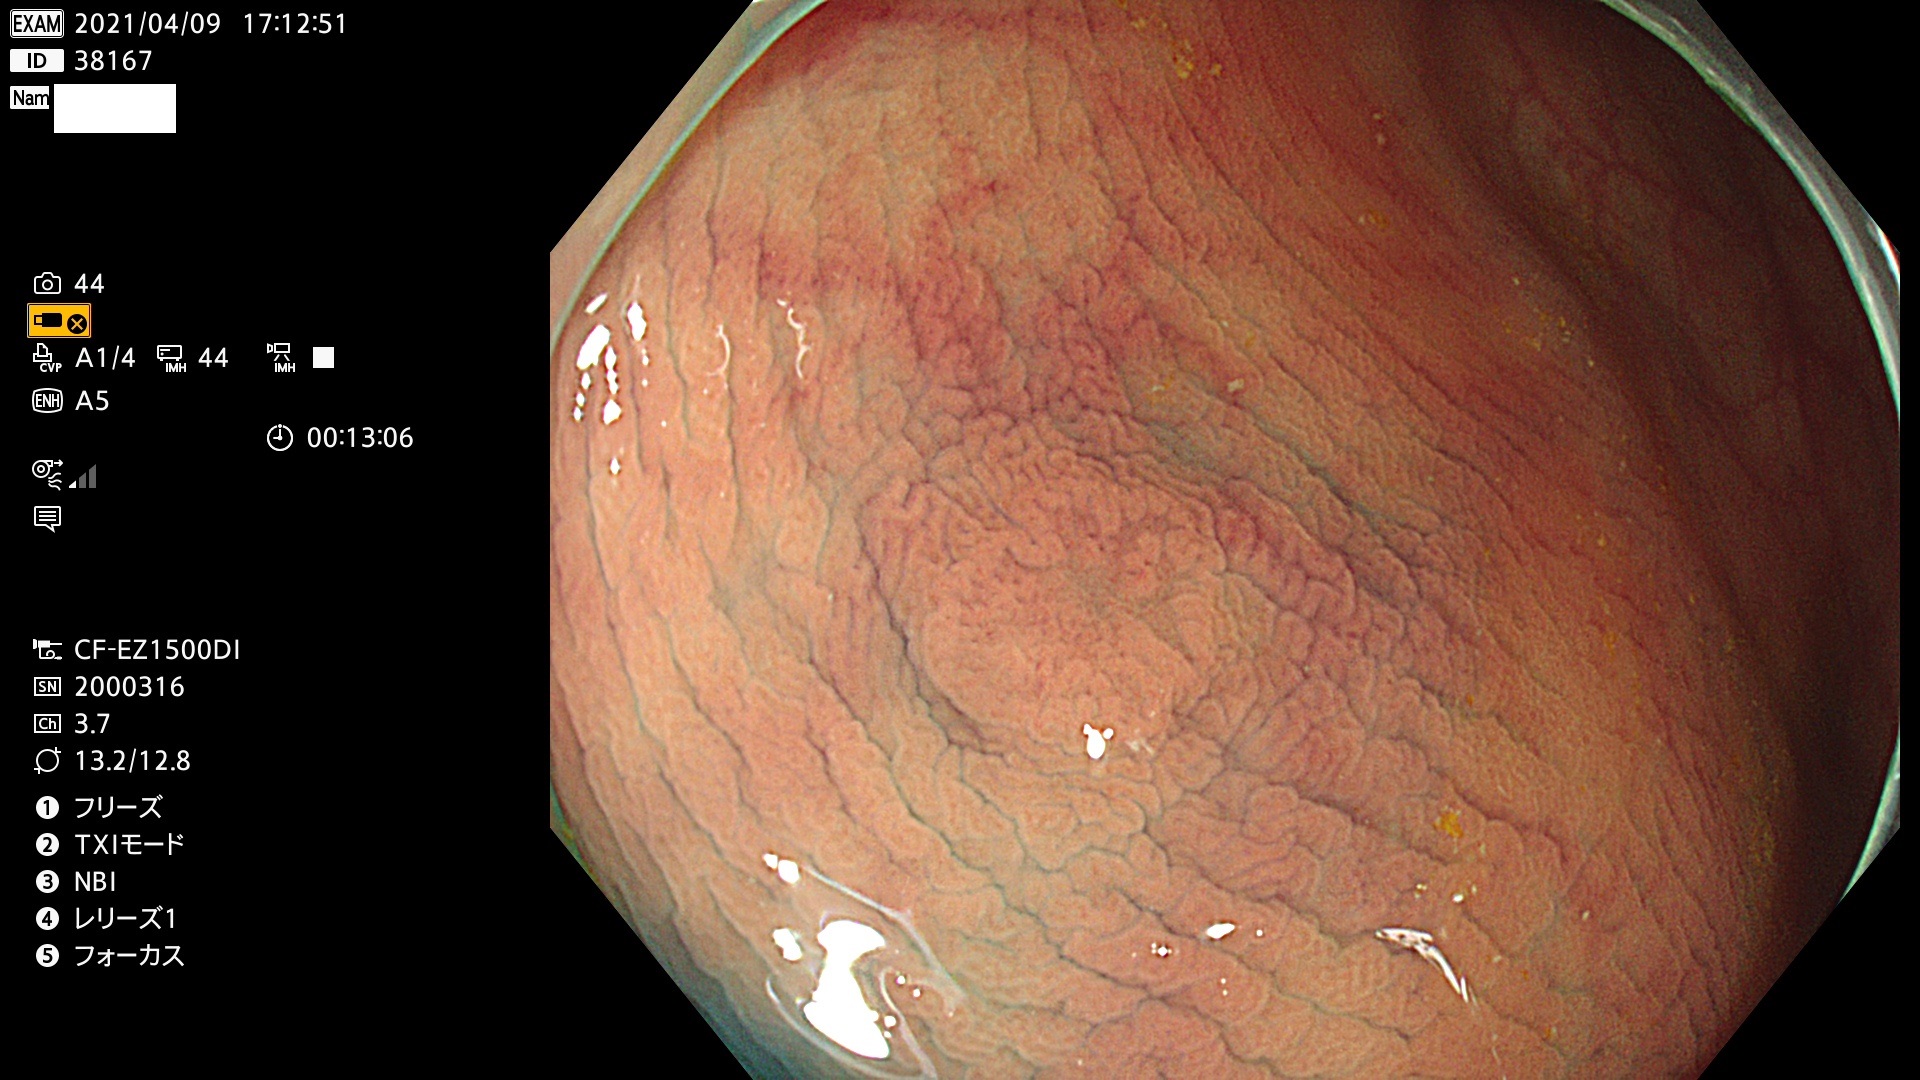

腺腫発見率 72 % (カルテ番号 38100〜38199の100名の方の検査結果で集計)大腸癌検診最新情報

以下のカルテ番号の方に腺腫(Adenoma,Group3〜5)が見つかりました(集計法)

38101 38103 38104 38106 38107 38108 38109 38110 38111 38112 38113 38114 38115 38117 38118 38122 38123 38124 38125 38126 38127 38128 38130 38131 38132 38135 38137 38138 38140 38141 38142(SSAPのみ) 38143 38144 38145 38146 38147 38148 38149 38150 38151 38152 38153 38154 38157 38158 38160 38161 38162 38164 38165 38166 38167 38168 38169 38172 38176 38177 38178 38181 38182 38183 38184 38187 38189 38190 38191 38192 38193 38194 38195 38196(SSAPのみ) 38198

発見困難で危険性の高い平坦型病変(上記100名より抽出) ![]()